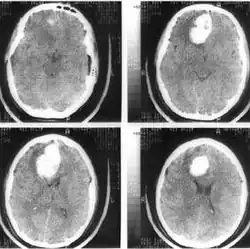

Компьютерная томография (КТ) и магнитно-резонансная томография (МРТ) — наиболее важные диагностические исследования при инсульте. КТ в большинстве случаев позволяет чётко отдифференцировать «свежее» кровоизлияние в мозг от других типов инсультов, МРТ предпочтительнее для выявления участков ишемии, оценки распространённости ишемического повреждения и пенумбры. Также с помощью этих исследований можно выявлять первичные и метастатические опухоли, абсцессы мозга и субдуральные гематомы. Если наблюдается ригидность затылочных мышц, но отсутствует отёк диска зрительного нерва, люмбальная пункция в большинстве случаев позволит быстро установить диагноз кровоизлияния в мозг, хотя при этом сохраняется незначительный риск возникновения синдрома «вклинения» мозга. В случаях, когда есть подозрения на эмболию, люмбальная пункция необходима, если предполагается применение антикоагулянтов. Люмбальная пункция имеет также важное значение для диагностики рассеянного склероза и, кроме того, может иметь диагностическое значение при нейроваскулярном сифилисе и абсцессе мозга[39]. При недоступности КТ или МРТ необходимо выполнить эхоэнцефалографию и люмбальную пункцию.